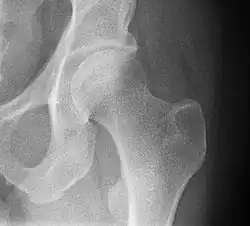

En radiographie standard[3] :

- le bassin de face Debout permet d'évaluer l'épaisseur de l'interligne articulaire et la statique du bassin (recherche d'une bascule du bassin en cas d'inégalité de longueur des membres inférieurs). Ce cliché montre un cintre cervico-obturateur qui doit être régulier ;

- le faux profil de Lequesne permet de mesurer la couverture antérieur et d'évaluer l'interligne articulaire dans le sens antéro-postérieur ce qui est un élément diagnostique plus sensible lors du dépistage de la coxarthrose débutante ;

- le profil chirurgical (d'Arcelin ou de Ducroquet) est l'examen simple ne nécessitant pas la mobilisation de l'articulation, à la recherche d'une fracture du col fémoral ;

- le profil urétral utile dans la recherche d'une ostéonécrose de la tête fémorale.

En radiologie conventionnelle, la coxométrie est la mesure des angles formés par les différentes structures de la hanche et de diagnostiquer des anomalies constitutionnelles ou acquises.